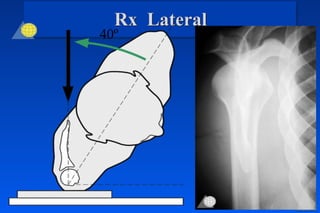

Rx Anteroposterior

40º 40º

Rx Lateral

40º